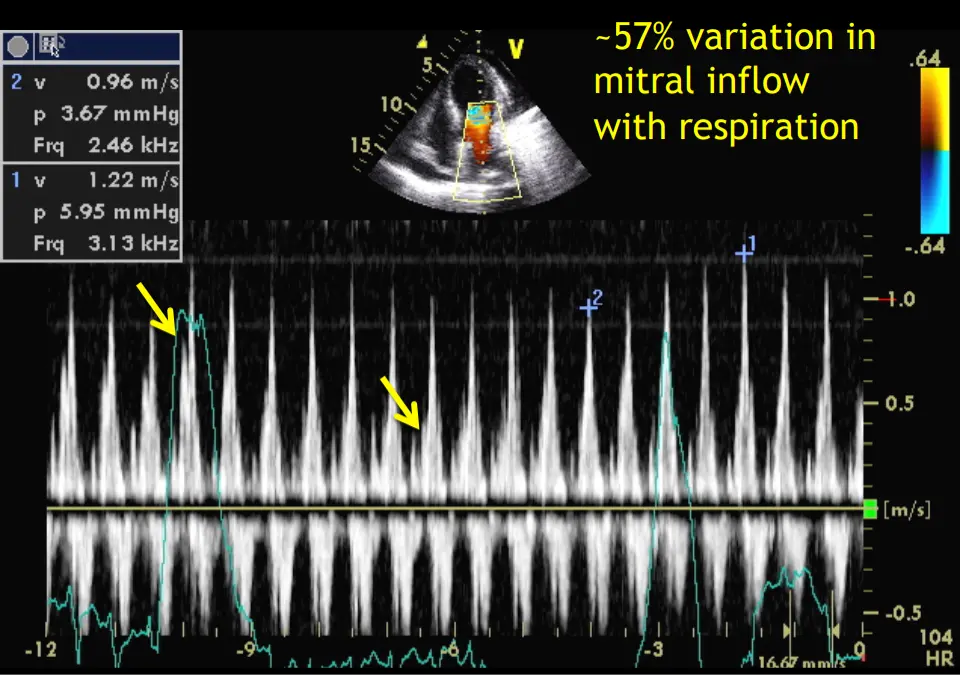

- Increased respiratory variation in mitral (> 25%) and tricuspid (> 40%) mitral inflow velocities

- ⚠️ ASE guideline documents have used mitral >30% and tricuspid >60% as well.

- Using the measured peaks (➕1 and ➕2), the variation is 21%, . The peaks as designated by the arrows in Dr. Shah’s talk are probably the peaks you should be using, which gives your 57% variation, i.e. concerning for tamponade